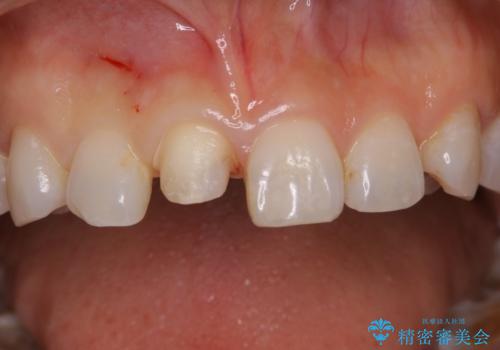

何度も欠けてしまう前歯を被せ物で治療

- プラスチックで治療している前歯が何度も欠けてしまうとお悩みで来院された方です。

歯全体を覆うクラウンにて治療を行いました。